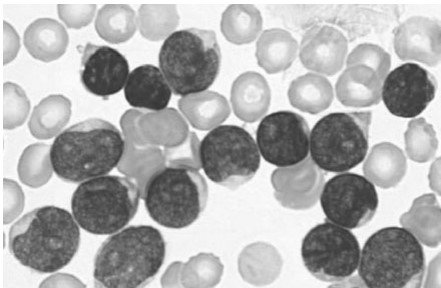

Uma mulher de 28 anos observou perda de movimentação fetal com 36 semanas de gestação por datas. Não se ouviam batimentos cardíocos fetais com 40 semanas pela DUM, quando a paciente foi vista novamente. O útero media 30 cm a partir da sínfise até o fundo.

I) O que que a amniocentese provavelmente iria revelar neste caso?

A morte fetal é bastante provável. (0,05 p). Caso a amniocentese seja realizada um líquido escuro (0,05 p) que pode ser causado por mecônio (0,05 p) ou sangramento (0,05 p).

II) Que teste seria valioso para realizar neste momento?

Na presença de morte fetal há algum tempo, a mãe pode desenvolver uma coagulopatia de consumo (0,05 p). Uma coagulograma seria o melhor teste neste momento (0,05 p).

III) Qual é a complicação materna mais bem reconhecida que pode ocorrer neste caso?

Um feto morto retido no útero por mais de 5 semanas (0,05 p) provavelmente vai provocar uma hipofibrinogenemia (0,05 p); portanto, a capacidade de coagulação materna deve ser avaliada (0,05 p), pelo menos 1 vez por semana (0,05 p). Há indicação para expulsão do feto morto.